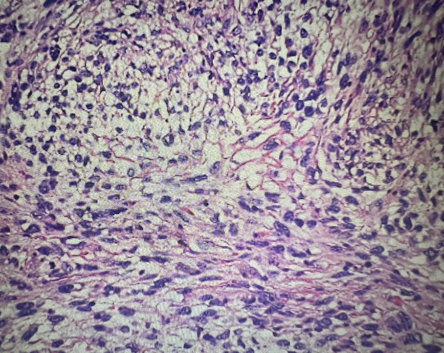

A 57-year-old man, with history of cigarettes smoking, presented with obstructive lower urinary tract symptoms (LUTS) and intermittent hematuria. Ultrasonography revealed a 4 × 5 cm urinary bladder tumor on the left lateral wall, with normal-appearing upper urinary tracts. Endoscopy revealed a large, polypoid tumor within the bladder; therefore, underwent transurethral resection of bladder tumor (TURBT). Histopathological examination revealed pT2 sarcomatoid carcinoma Figure 1. Radical cystoprostatectomy with bilateral extended pelvic lymphadenectomy and urinary diversion was subsequently performed. Definitive histopathology confirmed a pure sarcomatoid carcinoma without perivesical involvement and 21 lymph nodes negative for malignancy. Additionally, the prostate, bilateral seminal vesicles, vas deferens, and ureteric margins were free of tumor (pT2, N0, Mx) so did not received adjuvant chemotherapy. At two years of follow-up, he remains alive with no evidence of disease.

Figure 1 Histopathology slide showing sarcomatoid carcinoma presenting round cells, giant pleomorphic cells and spindle-shaped anisokaryocytic cells.